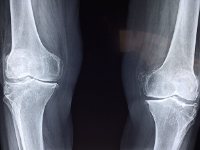

무릎 관절에 좋은 음식 무릎 관절 관리 방법 등 정보에 대해 알아보도록 하겠습니다. 무릎 관절은 우리 몸에서 가장 중요한 부위 중 하나입니다. 다리를 지탱하고, 움직임을 제공하는 기능을 수행합니다. 무릎 관절은 대개 체중과 운동에 의해 과부하가 걸리기 때문에, 연령과 상관없이 다양한 질환과 손상이 발생하기 쉽습니다. 무릎 관절 질환에는 퇴행성 관절염, 무릎 관절염, 슬관절 연골손상 등이 있습니다. 이러한 질환은 무릎 관절 통증, 붓기, 운동 제한 등의 증상을 유발합니다. 무릎 관절 건강을 유지하기 위해서는 적절한 운동, 올바른 식습관, 적절한 체중 유지, 적절한 자세 등이 필요합니다. 무릎 관절 질환의 예방과 관리를 위해서는 정기적인 건강 검진과 치료가 필요합니다.

무릎 관절염 원인

무릎 관절염의 원인은 여러 가지가 있지만, 가장 일반적인 원인은 연령, 체중, 유전적인 요인, 부상, 직업적 요인, 불규칙한 운동 등이 있습니다.

- 연령: 노화로 인해 무릎 관절 손상이 발생할 가능성이 높습니다. 연령이 들면서 연골이 더 얇아지고 윤활유 분비가 감소하게 되어 무릎 관절의 충격 흡수 기능이 감소합니다.

- 체중: 과체중은 무릎 관절에 대한 부담을 높이며, 무릎 관절의 염증을 일으키고 무릎 관절염 발병 위험을 높입니다.

- 유전적 요인: 유전적 요인도 무릎 관절염의 원인 중 하나입니다. 가족력이 있는 경우 무릎 관절염 발병 위험이 높아집니다.

- 부상: 무릎 관절 부상은 무릎 관절염의 발병 위험을 높입니다. 특히, 골절, 연골손상, 인대 손상 등이 무릎 관절염을 일으키는 원인이 될 수 있습니다.

- 직업적 요인: 직업적 요인으로 인해 무릎 관절 부담이 커지면 무릎 관절염 발병 위험이 높아집니다. 예를 들어, 무릎을 자주 굽히거나 일어설 필요가 있는 직업, 장시간 서 있는 직업 등이 그러합니다.

- 불규칙한 운동: 무릎 관절 부하를 지나치게 높이는 불규칙한 운동은 무릎 관절의 염증을 유발합니다.

무릎 관절염은 위와 같은 여러 요인들이 복합적으로 작용하여 발생할 수 있습니다. 따라서 무릎 관절염 예방 및 치료를 위해서는 건강한 식습관과 운동 습관을 유지하며, 무릎 관절에 대한 적절한 관리가 필요합니다.

무릎 관절염 증상

무릎 관절염의 증상은 다음과 같습니다.

- 통증: 무릎 관절염의 가장 일반적인 증상은 무릎 주변의 통증입니다. 특히, 오랫동안 앉거나 서 있거나 움직일 때 더 심해집니다.

- 뻣뻣함: 무릎 관절염은 무릎 관절의 뻣뻣함을 유발합니다. 무릎 관절의 움직임이 제한되며, 일어나거나 앉는 것이 어려울 수 있습니다.

- 부종: 무릎 관절염으로 인해 무릎 주변의 부종이 발생할 수 있습니다. 부종은 무릎 관절에 더 많은 압력을 가해 더 많은 통증을 유발합니다.

- 열감: 무릎 관절염은 관절 주위 조직의 염증으로 인해 무릎 주변에서 열감을 느낄 수 있습니다.

- 소리: 무릎 관절염은 무릎 관절에서 윤활제 분비 감소로 인해 뼈가 마찰되어 생기는 부적합한 소리를 유발할 수 있습니다.

무릎 관절염의 증상은 진행되는 정도에 따라 다양합니다. 초기에는 가벼운 통증이 있을 수 있으나, 진행되면서 무릎 관절의 기능 저하와 더 심한 통증이 발생할 수 있습니다. 무릎 관절염이 의심되면, 증상이 심화되기 전에 적극적인 치료와 예방 조치를 취하여 증상의 악화를 방지해야 합니다.